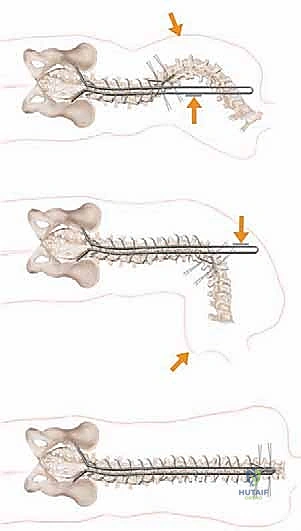

Biomechanically, the unit rod construct is a masterpiece of load-sharing and stress distribution. By utilizing a single, continuous, pre-contoured rigid rod (typically 1/4 inch or 3/16 inch stainless steel) and securing it at every available segmental level with sublaminar wires, the construct dissipates corrective forces across the entire length of the spine. This minimizes the stress concentrated at any single bone-implant interface, drastically reducing the risk of implant pullout in osteopenic bone. The primary corrective maneuver is a powerful cantilever force. The distal limbs of the unit rod are first docked into the ilium. The proximal U-shaped portion, which initially stands proud of the kyphoscoliotic thoracic spine, is then gradually leveraged down to the midline. This maneuver translates the spine to the rod, simultaneously correcting the coronal deformity, restoring sagittal contours, and forcefully leveling the pelvis.

The unit rod must be custom-contoured to match the patient's ideal sagittal profile, incorporating appropriate thoracic kyphosis and lumbar lordosis. The distal limbs are bent to perfectly match the trajectory of the intra-iliac pathways prepared earlier.

The correct width of the U-rod is selected to sit comfortably across the laminae. The rod is then introduced to the sterile field. The distal limbs are simultaneously impacted into the bilateral iliac holes. At this stage, the proximal U-portion of the rod will be standing high above the thoracic spine due to the uncorrected deformity.

5. The Cantilever Reduction Maneuver

With the pelvis securely docked, the cantilever reduction begins. The surgeon forcefully pushes the proximal U-portion of the rod down toward the thoracic spine. This maneuver requires significant physical force and utilizes the rod as a massive lever arm.

As the rod is brought down to the spine, it translates the apical vertebrae toward the midline, correcting the scoliosis, while simultaneously forcing the elevated hemi-pelvis down, correcting the pelvic obliquity.

Once the rod is approximated to the spine, the sublaminar wires are sequentially tightened around the rod.

Tightening begins at the apex of the curve to draw the spine to the rod, and then proceeds proximally and distally. The wires must be tensioned symmetrically to avoid asymmetric pull-out.